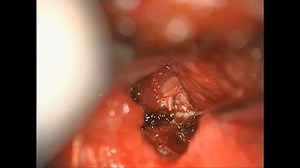

- Hemilaminectomy L4 5

-L5 Hemilaminectomy - Laminectomy